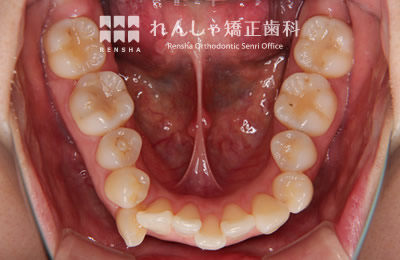

大きながたつきを歯列の拡大で改善しようとすると歯周組織へのダメージや後戻りが問題になります。この様な場合はスペースを確保するために永久歯を抜歯する方法を選択します。歯を抜いてしまうことに不安もあるかと思いますが、抜歯矯正が長い目で見たときにいい結果になることも多いと思います。

治療前

治療中

治療後

| 主訴 | 叢生 |

|---|---|

| 診断名 | Angle Class I 叢生 |

| 初診時年齢 | 27歳0か月 |

| 装置名 | マルチブラケット装置 |

| 抜歯非抜歯 | 上下顎左右第一小臼歯の抜歯(合計4本) |

| 治療期間 | 2年5か月 |

| 費用の目安 | 約93万円+消費税(検査料金、都度の処置費用等も合わせた総額) |

| リスク副作用 | 歯の移動に伴う軽微な歯根吸収、歯槽骨吸収、歯肉退縮(本症例では軽度の歯肉退縮を認めた)、矯正器具装着中のカリエスリスク増大(本症例ではカリエス発生無し) |